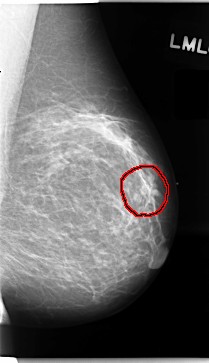

C_0059_1.RIGHT_MLO

LEFT_MLO LINES 4712 PIXELS_PER_LINE 2712 BITS_PER_PIXEL 12 RESOLUTION 50 OVERLAY

FILE: C_0059_1.LEFT_MLO.OVERLAY

TOTAL_ABNORMALITIES 1

ABNORMALITY 1

LESION_TYPE MASS SHAPE IRREGULAR MARGINS SPICULATED

ASSESSMENT 5

SUBTLETY 4

PATHOLOGY MALIGNANT

TOTAL_OUTLINES 1

BOUNDARY